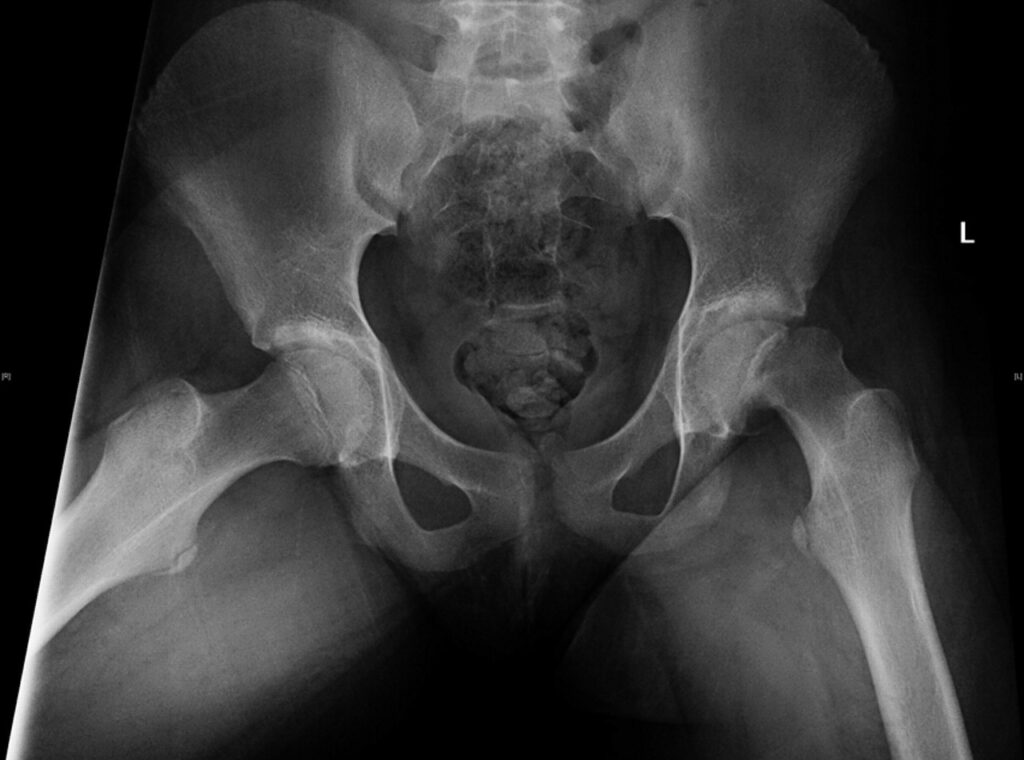

It is a condition typically seen in the elderly but can also rarely occur in young individuals. In osteoporosis among […]